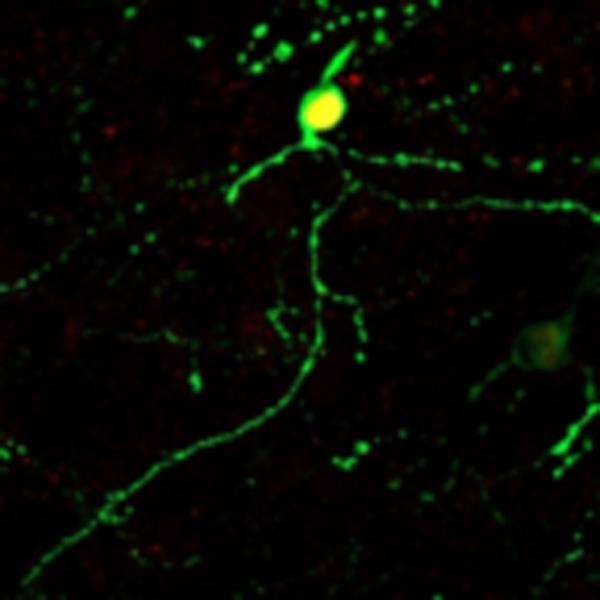

In this work, Prof. Chen and his team further extended their neuroregenerative technology from the brain to the spinal cord. They first demonstrate that overexpression of NeuroD1 in dividing reactive astrocytes through retrovirus can successfully convert astrocytes into neurons in the injured spinal cord. The advantage of using retrovirus is that they only express transgene such as NeuroD1 here in dividing glial cells, but not non-dividing neurons, eliminating the possibility of direct NeuroD1 expression in preexisting neurons. To increase the efficacy of neuronal conversion and pave the way for future translational application, Chen and team further developed adeno-associated viral system (AAV) to deliver NeuroD1 to both dividing and non-dividing astrocytes under the control of astrocytic promoter GFAP and confirmed direct astrocyte-to-neuron conversion in the spinal cord. AAV vector is commonly used for gene therapy because of its relatively low immunogenicity and high efficiency of spreading in various tissues including nervous tissue. Interestingly, Chen and team found that NeuroD1 alone generated mainly excitatory glutamatergic neurons, whereas addition of another transcription factor Dlx2 significantly increased the proportion of inhibitory GABAergic neurons, indicating that using different combinations of transcription factors can generate different subtypes of neurons.

Another important factor affecting neuronal fate after conversion is local environment. Chen's team designed a set of side-by-side comparison experiments by injecting the same NeuroD1 vector into the mouse cortex or spinal cord. After one month, they found that the neurons converted from cortical astrocytes showed cortical neuron markers but not spinal cord markers, whereas neurons converted from spinal astrocytes showed spinal neuron markers but not cortical markers, indicating the importance of local environment in shaping the neuronal fate after conversion.